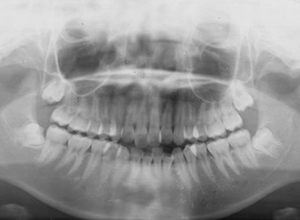

X-Ray

X-Ray所見

パノラマ所見 上下顎左右側8は埋伏していた。